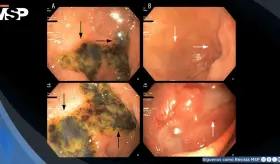

Paciente con insuficiencia multiorgánica, hipoglucemia severa y úlceras duodenales tras inyectarse intencionalmente ocho veces su dosis habitual de semaglutida, en el primer caso documentado de intento de suicidio con este fármaco antidiabético.